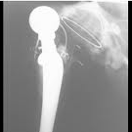

The x-rays below show what cemented, un-cemented and hybrid hip replacements look like.You can also see how the surgeon can measure the patients leg length post operatively on the hybrid x-ray.

Accurate positioning of implants.

Most routine hip replacements can be implanted relatively accurately, but occasionally a patient may have unusual anatomy. Computer Aided Surgery has been demonstrated to improve precision and accuracy with joint replacement surgery. It may be used to optimise implant position and reduce the incidence of poorly positioned implants. This may affect the length of time an implant lasts. Less than 1% of surgeons use Computer Aided Navigation in hip replacement surgery.